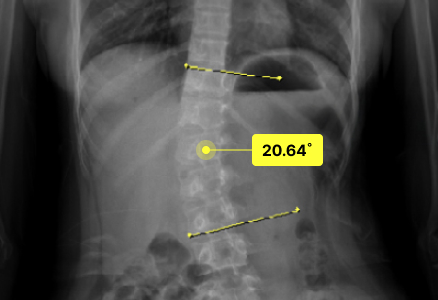

척추측만으로 휘어진 허리 때문에 일상조차 버거웠던 환자분들이

두드림의 교정치료를 통해 뚜렷한 변화와 회복을 경험하고 있습니다.

· 각 치료사례는 환자분들에게 사전 동의를 받아 동일 조건에서 촬영된 이미지입니다.

· 개인에 따라 치료 결과가 달라질 수 있으니 의료진과 충분한 상담 후 치료를 진행하시길 권장드립니다.